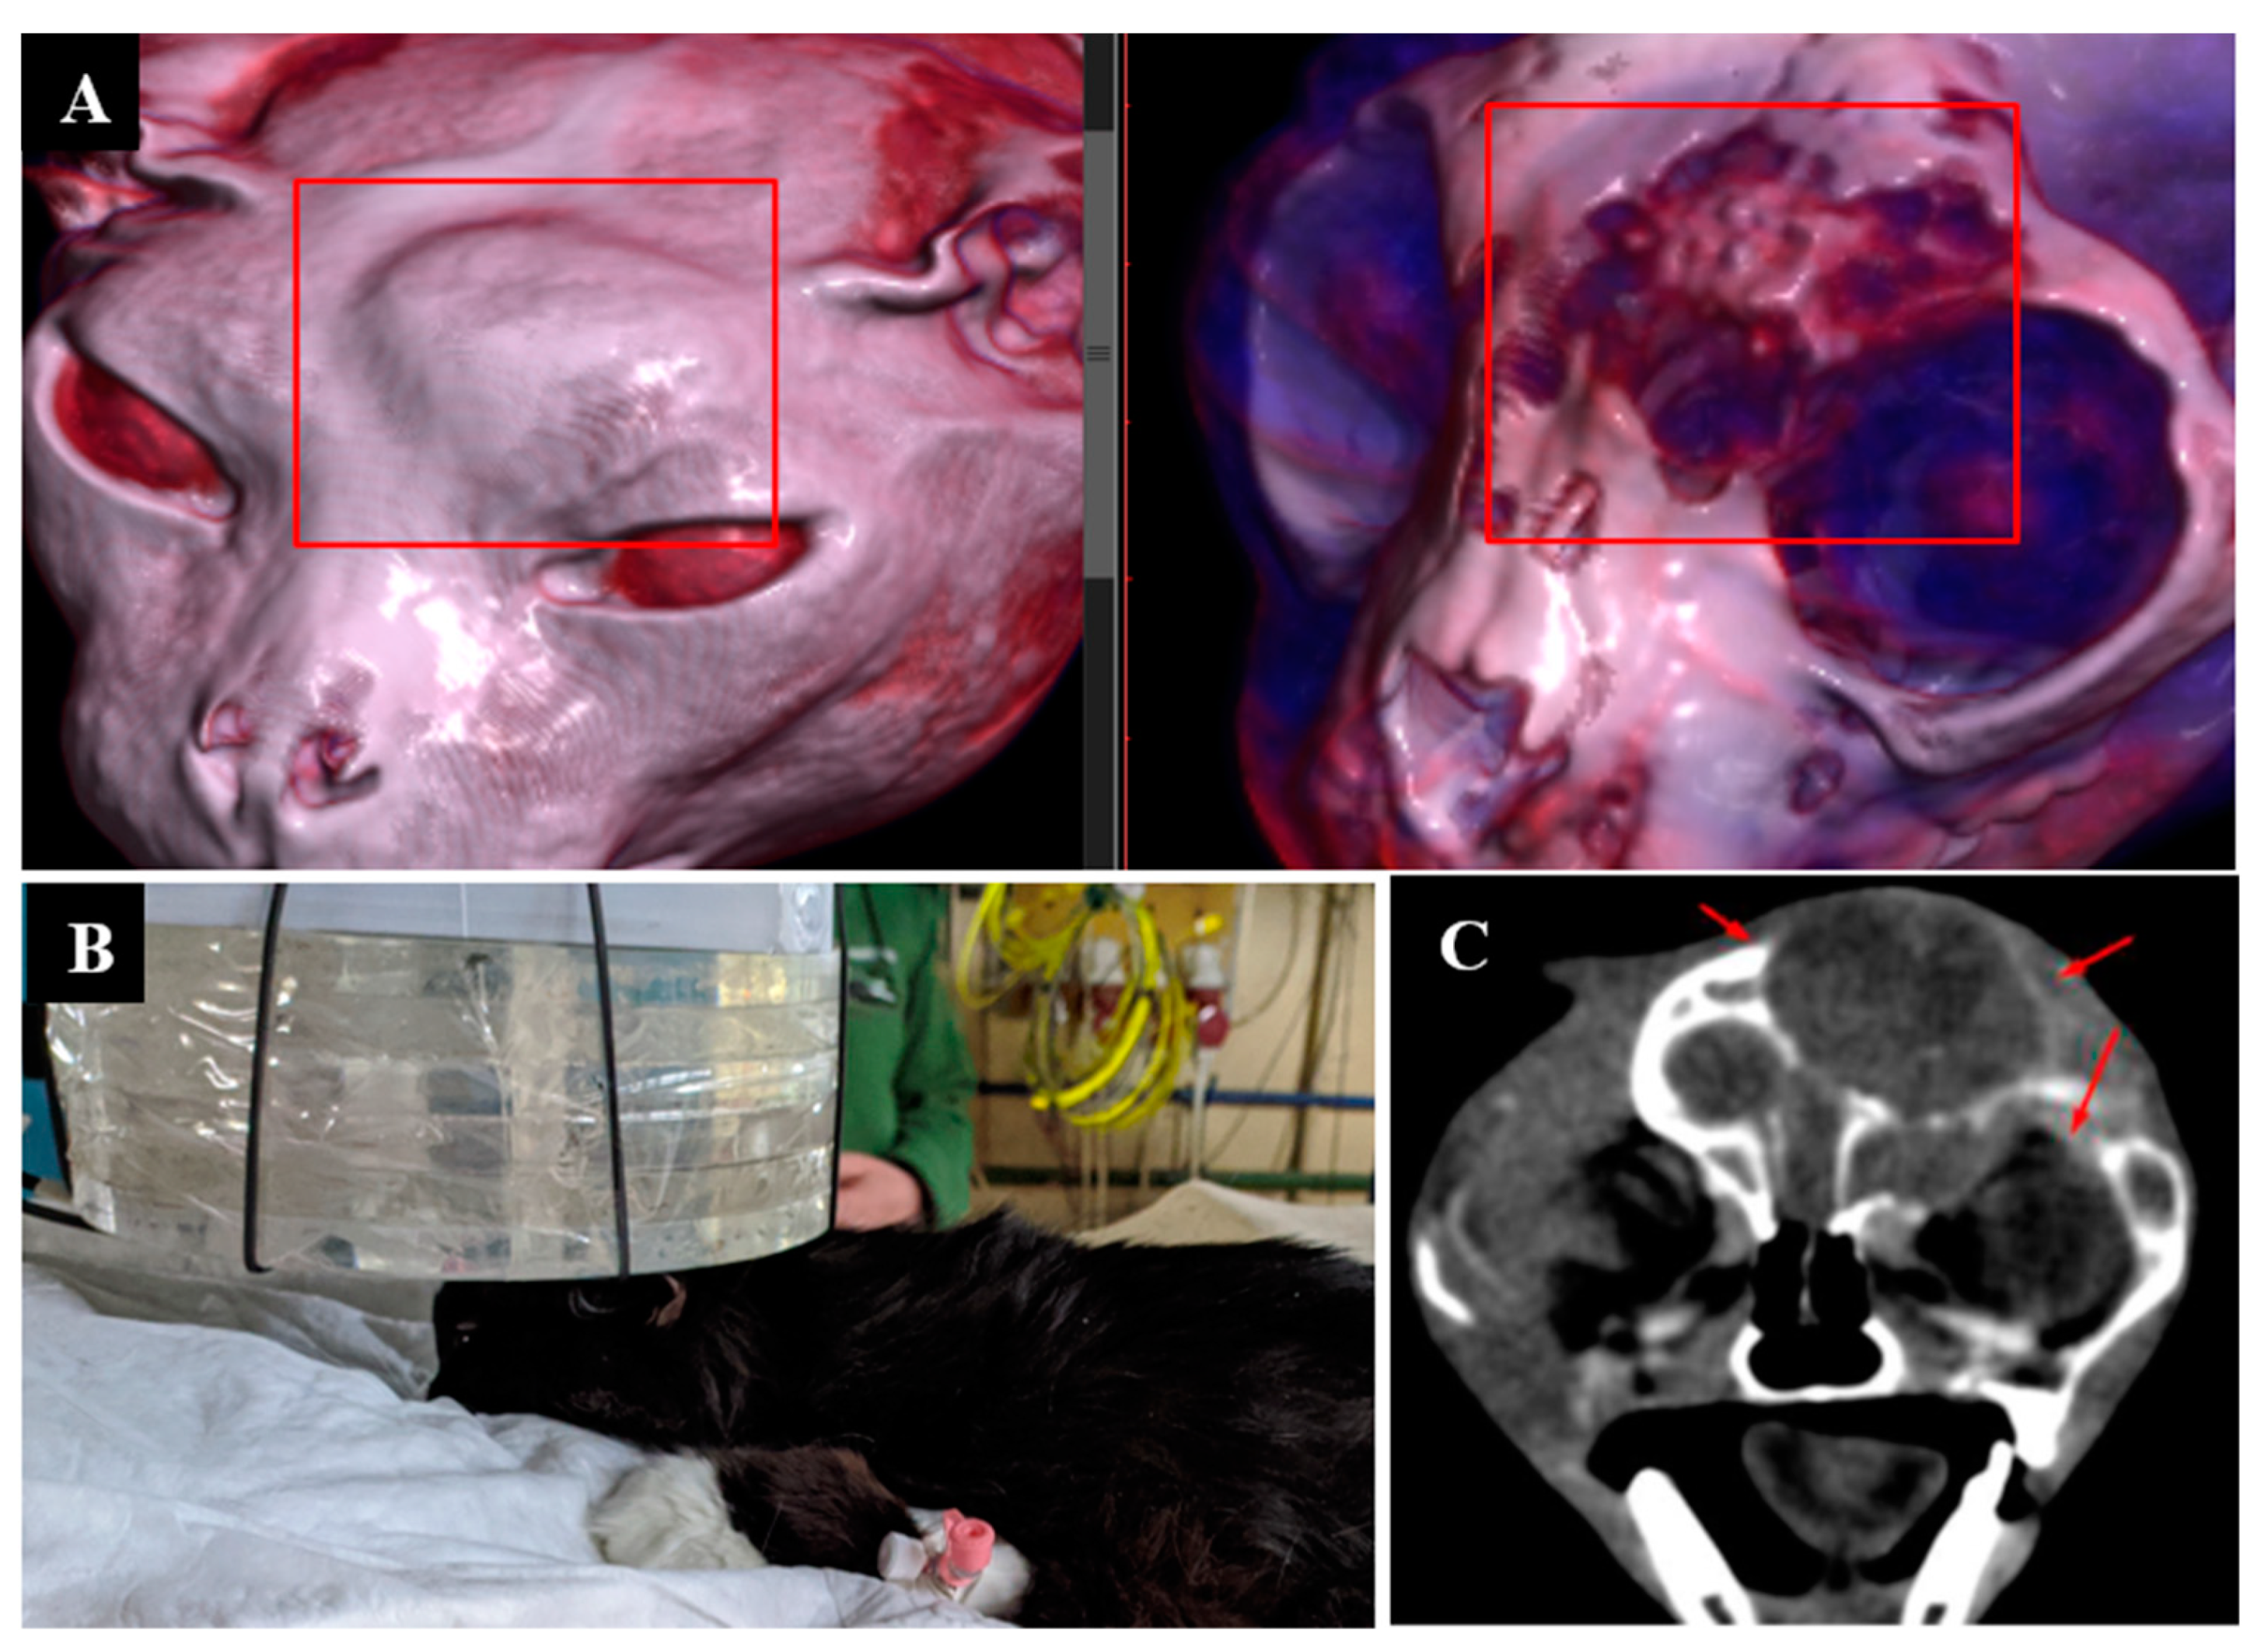

3.1. Case 1

3.2. Case 2

3.3. Case 3

3.4. Case 4

3.5. Case 5

3.6. Case 6

3.7. Case 7

3.8. Case 8

3.9. Case 9